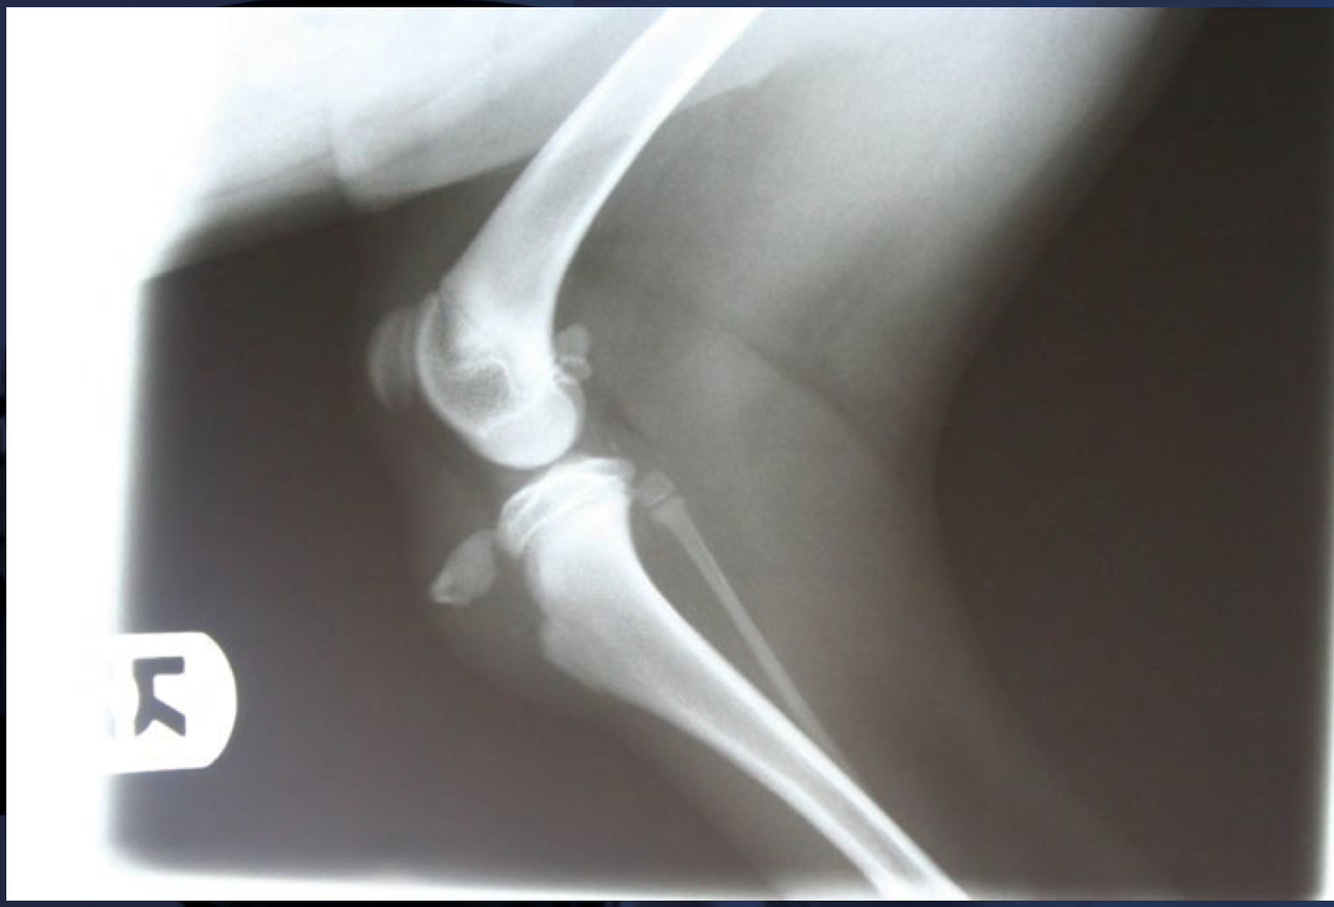

Pathological fracture:

A

neoplasia